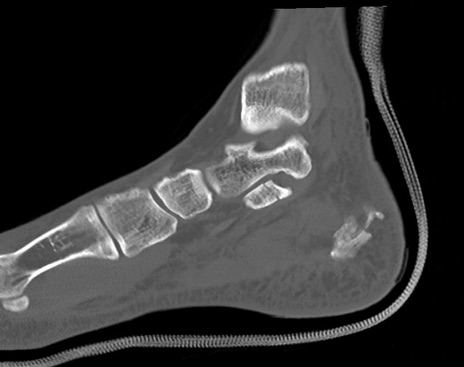

症例37 左足関節CT(矢状断像)

左足関節CT